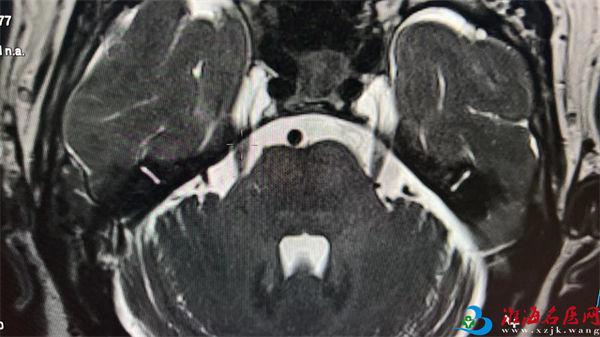

磁共振MRI成像是一种多角度、多参数的医学成像技术,特别是在软组织检查上具有优良的组织对比度和空间分辨率,国际上从一九八二年才正式用于临床。它采用静磁场和射频磁场使人体组织成像,在成像过程中,没有电离辐射,即使不用造影剂也可获得高对比度的清晰图像,它能够从人体分子内部反映出人体器官失常和早期病变。磁共振检查在很多地方优于X线CT,核磁共振机器简单来说,就是用一个强大的磁场,让身体里的氢原子产生共振。磁共振检查扫描时间较长,噪声较大且影响因素颇多,相对于CT有着更为严苛的扫描条件。以下我们将从大家都很关心和疑惑的几个点具体讲讲此项检查。

1、 对软组织分辨力高:能清晰显示脑、脊髓、肌肉、肌腱、滑膜、脂肪等软组织的病变情况,这是其突出优势。

2、多方位成像:可以获得冠状位、矢状位、横轴位及任意斜位的图像,有助于更全面了解病变的位置和范围。

影像科现拥有西门子高端Vida3.0T磁共振成像系统,此系统是目前国际上高精尖的检查设备,具有成像清晰、扫描快捷的优势,投入使用后,为患者提供更加清晰的影像资料,且具有影像云存储功能,检查者通过云平台即可查询报告及全部图像资料。